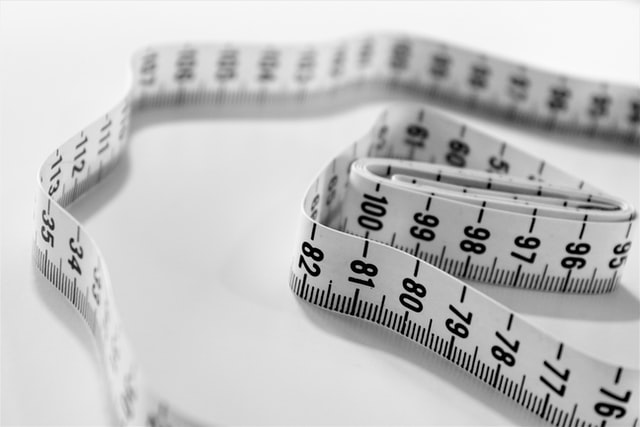

经历了化疗、免疫治疗、靶向治疗之后的肿瘤不但没有退缩,而且还在继续生长,以至于局部破溃出血,患者生活质量受到严重影响,甚至无法直立行走,来到中山一院就诊时,她胸前的巨大肿瘤已超过20cm,累及整个左胸前区皮肤。

▲患者胸前的巨大肿瘤已超过20cm

虽然多线姑息治疗效果欠佳,但患者还是希望能够通过手术来切除胸前这个巨大的肿块。此时的她除了肿瘤状况以外,还伴有严重的贫血表现,血红蛋白最低达49g/L,红细胞只有1.89 X 10^12/L,出现了低白蛋白血症等消耗性改变。

手术台上,肿瘤与术前评估一致,直径超过20cm,表面多处破溃,伴渗血及脓性分泌物。由于肿瘤与胸大肌、胸小肌紧密黏连,肿瘤内部感染和坏死,肿瘤周围血管增生,导致操作难度大,术中出血风险高。所幸,整个团队配合默契,将肿瘤连同胸大肌、部分胸小肌一起整体切除,最后利用负压引流装置封闭创面。